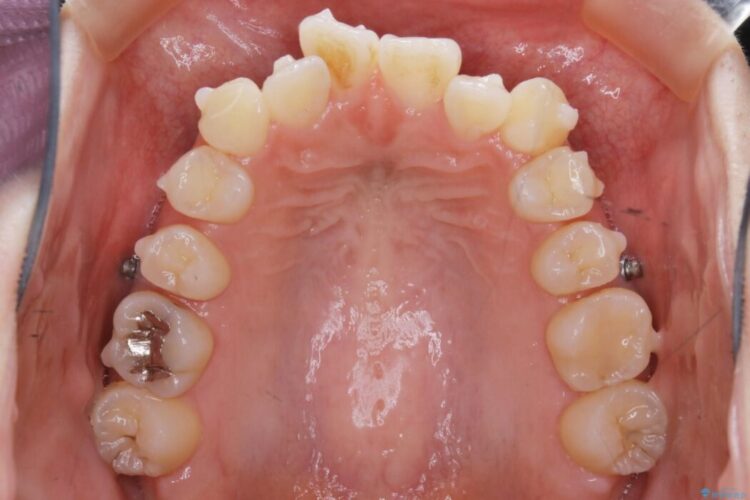

本症例では奥歯から順に移動させるため前歯の変化を感じるには時間が掛かりましたが、インビザライン装置とマイクロインプラントを併用することで健康な歯を抜歯することなく歯列をきれいに整えることができました。

マイクロインプラントとは矯正治療で使用する小さなネジのことです。

このネジを支点とし歯を引っ張ることで効率的に動かすことで、治療期間の短縮や従来の矯正治療では難しかった動きも対応が可能になります。